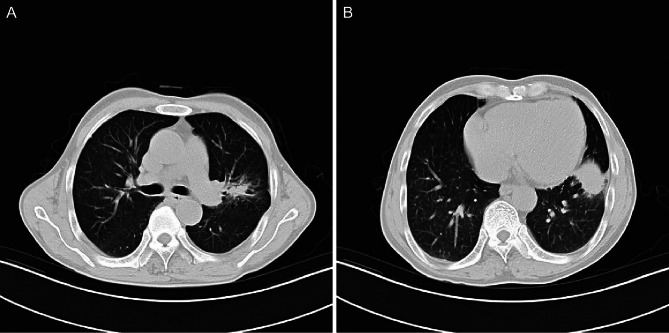

Case presentation: A 66-year-old man presented with cough, sputum, chest tightness and weight loss persisting for 1 month. Chest X-ray revealed a space-occupying lesion in the left lung. Further CT imaging demonstrated irregular soft tissue masses in both the upper and lower lobes of the left lung. Although the imaging findings suggested lung cancer, the final pathological diagnosis confirmed AFOP. The patient was treated with methylprednisolone, resulting in substantial improvement of the upper lobe lesion, whereas the lower lobe lesion showed minimal response. Following the addition of mycophenolate mofetil, the lower lobe lesion decreased substantially. Multiple lung biopsies confirmed the diagnosis of AFOP, with no evidence of a malignant tumour.

Conclusions: Acute fibrinous and organising pneumonia presents with non-specific imaging findings, and when manifesting as a mass-like lesion, it may be misdiagnosed as lung cancer. Pathological examination remains essential for diagnosis. Close monitoring of the clinical response is crucial during treatment, and the treatment plan should be tailored to individual patient needs.